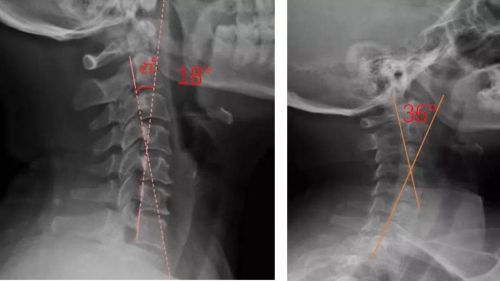

患者適配前后側位X光,佩戴前18°,適配后36°

對于頸椎病患者,合理設計的頸椎枕,能夠緊密適合頸椎,矯正頸椎生理曲度;再根據(jù)頸椎曲度改善情況,隨時間慢慢調(diào)整3D打印頸椎枕曲度,使變直的頸椎逐漸形成正常的生理曲度,改善頸肩痛的癥狀。